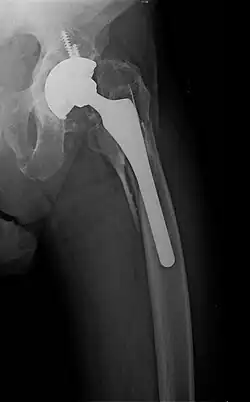

- Periprosthetic fracture – a fracture at the point of mechanical weakness at the end of an implant.

When the initial post-fracture oedema or swelling goes down, the fracture may be placed in a removable brace or orthosis. If being treated with surgery, surgical nails, screws, plates, and wires are used to hold the fractured bone together more directly. Alternatively, fractured bones may be treated by the Ilizarov method, which is a form of an external fixator.

Surgical methods of treating fractures have their own risks and benefits, but usually, surgery is performed only if conservative treatment has failed, is very likely to fail, or is likely to result in a poor functional outcome.[42] With some fractures such as hip fractures (usually caused by osteoporosis), surgery is offered routinely because non-operative treatment results in prolonged immobilisation, which commonly results in complications including chest infections, pressure sores, deconditioning, deep vein thrombosis (DVT), and pulmonary embolism, which are more dangerous than surgery.[43] When a joint surface is damaged by a fracture, surgery is also commonly recommended to make an accurate anatomical reduction and restore the smoothness of the joint.